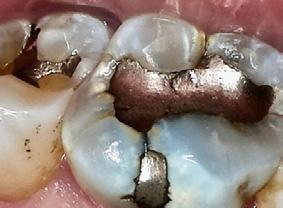

Today, approximately 40% to 50% of dental offices use digital intraoral scanning, and this percentage is only expected to grow.1 Current systems include a scanner with the head created to fit within the oral cavity to capture files of the entire dentition. The files can be used to create restorations as well as appliances either within the dental office or via a lab. While digital intraoral scanning once focused solely on restorative needs, the opportunities for its use have expanded to applications in orthodontics and pathologies such as caries, erosion, and oral cancer. In modern dental practices, this technology can also be integrated into the dental hygiene appointment.1-4

Dental team members use digital scanning for a variety of reasons. Dentists utilize digital impressions to create crowns, veneers, inlays, onlays, occlusal guards, whitening trays, and to plan treatment for implants and orthodontics. Even though most of the scans are used by dentists, other team members help to acquire the digital scans. Dental assistants and dental hygienists may be asked to create scans.

Dental hygienists independently utilize digital scanning for education and motivation. Not only can the clinician educate the patient with the images, but the patient has a visual that is easily understood. These images contain powerful visuals of attrition, fractured teeth, abfraction, gingival recession, overjet, and crowding.4 Biofilm can be displayed after the application of disclosing solution.5 Separate photos are not required to capture the biofilm present when using digital scanning.